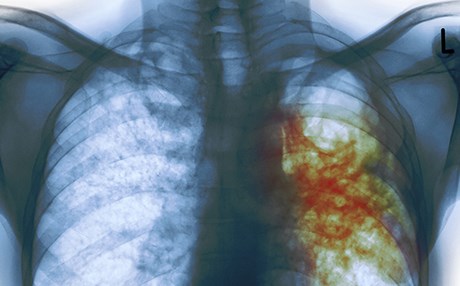

نەخۆشی سیل بەهۆی بەکتریای مایکۆبەکتریەم تیبی تووشی مرۆڤ دەبێت و زۆرتر کار لە سییەکانی مرۆڤ دەکات، بەڵام ئەندامەکانی دیکەش مەترسی تووشبوونیان هەیە، سیل بەیەکێك لە 10 هۆکارە سەرەکییەکانی مردن دادەندرێت و دەتواندرێت چارەسەر و رێگری بکرێت.